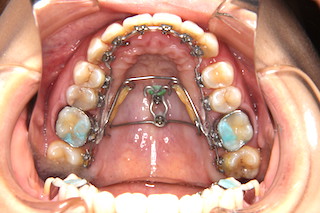

上顎・・見えない位置のインプラントで奥歯を更に奥へと動かします

側面・・上下とも歯茎のラインもそろってきました!

このケースでは矯正用インプラントを併用することによりヘッドギアーやエラスティックなどの自助努力なしに装置装着から撤去まで約2年2ヶ月と比較的短期間で治療することが出来ました。